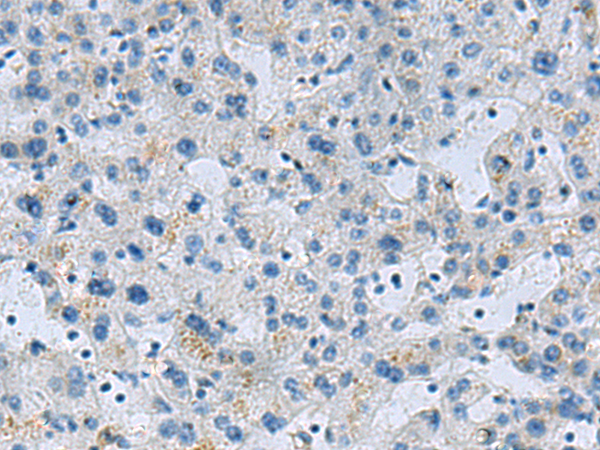

分类: 科研抗体货号: P06463别名: EHB21应用: IHC反应种属: Human, Rat